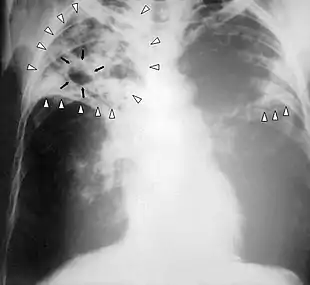

![]() | |

| Chest X-ray of a person with advanced tuberculosis: Infection in both lungs is marked by white arrow-heads, and the formation of a cavity is marked by black arrows. | |